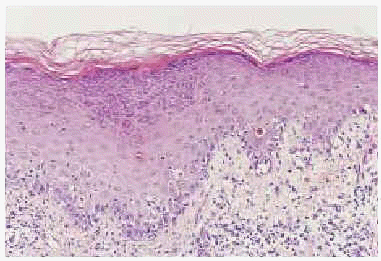

Un varón de 35 años de edad, con antecedentes de seminoma testicular con orquiectomía derecha en mayo de 1997, desarrolló en marzo de 1998 metástasis pulmonares que respondieron a tratamiento con 3 ciclos de BEP (bleomicina, etopósido y cisplatino). Dos años después fue diagnosticado de una leucemia mieloide M4 bifenotípica (linfo/monocitaria), con cariotipo de mal pronóstico [46XY 11q-, t(7,14)], secundaria muy probablemente a etopósido. Recibió tratamiento de inducción con citarabina e idarubicina, sin obtener respuesta. Posteriormente alcanzó la remisión completa con FLAG-Ida (fludarabina, adriamicina, dexametasona e idarubicina). En septiembre del 2000 se le realizó un trasplante alogénico de médula ósea procedente de un hermano con antígeno de histocompatibilidad (HLA) idéntico, previo acondicionamiento con fludarabina y melfalán. El donante presentaba dermatitis atópica, sin otros antecedentes de interés. La profilaxis inicial de EICH se realizó con ciclosporina y metotrexato. El paciente no presentó datos de EICH aguda y fue dado de alta con ciclosporina A, en dosis de 500 mg/día como único inmunodepresor. Se realizó un estudio de médula ósea, que fue normal, y dado que el paciente presentaba buen estado general, sin signos clínicos ni analíticos de EICH, al mes del trasplante se fue reduciendo de forma progresiva la dosis de ciclosporina. A los 50 días del trasplante mientras recibía una dosis de ciclosporina A de 200 mg/día, presentó un exantema maculopapuloso pruriginoso en la zona del escote, espalda y superficie de extensión de extremidades. Se realizó una biopsia cutánea del antebrazo, que mostró marcada espongiosis, exocitosis y formación de vesículas espongióticas (fig. 1). En la dermis papilar existía un marcado infiltrado inflamatorio perivascular superficial con presencia de macrófagos aislados. Se estableció el diagnóstico anatomopatológico de dermatitis espongiótica. No se observaron dermatitis de interfase ni queratinocitos necróticos. Ante este resultado histológico, y considerando que el donante era atópico se realizó determinación sérica IgE, que fue normal. Puesto que el paciente persistía con buen estado general, afebril, sin disnea, diarrea, dolor abdominal, ni otra sintomatología, y el estudio analítico, incluyendo el perfil hepático, no presentaba alteraciones significativas, se continuaron disminuyendo las dosis de ciclosporina A. Así, a los 65 días postrasplante, mientras tomaba una dosis de 100 mg/día, empeoraron las lesiones cutáneas, que afectaban ya a más del 80 % de la superficie corporal. En la exploración física presentaba (figs. 2 y 3) un gran número de pápulas de aspecto liquenoide, de distribución extensa por espalda, extremidades inferiores, cara anterior del tronco y, sobre todo, en miembros superiores, con afectación intensa del dorso de las manos. También se encontraron lesiones liquenoides en mucosa oral, en forma de reticulado blanquecino en ambas mucosas yugales. El paciente persistía con buen estado general, afebril, sin disnea, diarrea, ni otra sintomatología. El perfil hepático en este momento mostraba transaminasas glutamicooxalacética (GOT) de 676 U/l; glutamicopirúvica (GPT), 1.075 U/l, y gammaglutamiltranspeptidasa (GGT), 830 U/l; fosfatasa alcalina, 947 U/l, y bilirrubina, 2,5 mg/100 ml. Se realizó una nueva biopsia cutánea del dorso de la mano, que mostró una dermatitis de interfase con necrosis queratinocítica y degeneración vacuolar basal epidérmica y folicular, compatible con EICH (fig. 4). Con estos datos, el paciente fue diagnosticado de EICH aguda cutánea de grado 3 y hepática de grado 1. Se instauró tratamiento con prednisona, en dosis de 2 mg/kg/día, ácido ursodesoxicólico y ganciclovir profiláctico y se aumentaron las dosis de ciclosporina A a 500 mg/día. El paciente presentó una mejoría progresiva del cuadro cutáneo y hepático, con lo que se inició nuevo descenso progresivo de la inmunosupresión, con buena respuesta, sin aparición de nuevos signos de EICH hasta la actualidad.

Fig. 1.--Imagen panorámica donde se observa espongiosis con verticalización epidérmica y presencia de una vesícula espongiótica superficial (hematoxilina-eosina).